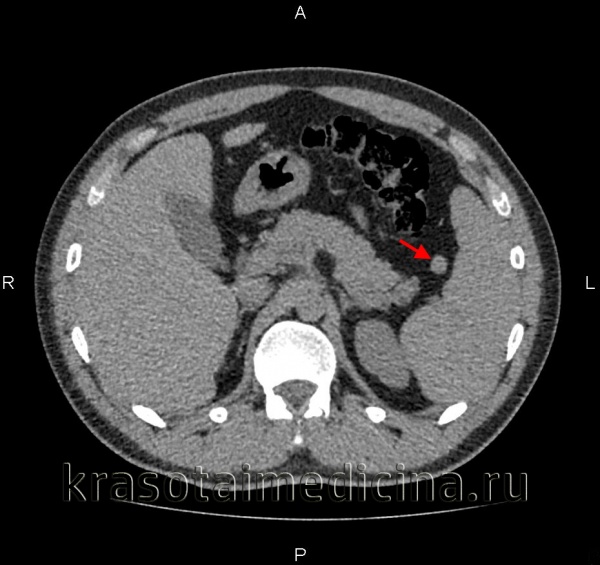

(Справа) На аксиальной КТ с контрастным усилением определяется большая киста, с множественными перегородками в структуре, не накапливающая контраст, занимающая большую часть объема селезенки, и только лишь небольшой участок ее паренхимы в задних отделах остается интактным.